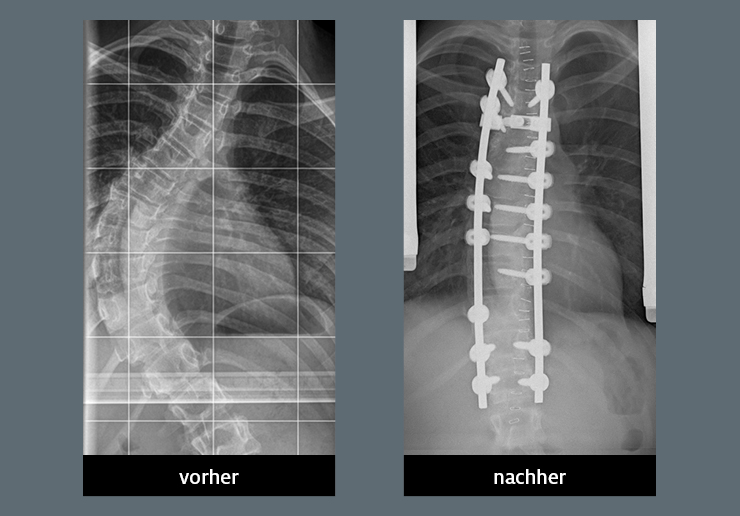

Source: megatellemd.pages.dev Skoliose Wirbelsäulenverkrümmung Schulthess Klinik , Galerie Vorher/Nachher-Schnellübersicht (Stand: 21.08.2014) Es wurden nur Vorher/Nachher-Bilder und Röntgenbilder der Skoliose-Galerie berücksichtigt. Für idiopathische Skoliosen kann man sich an den Gradzahlen der Krümmungen orientieren

Source: netcitzpu.pages.dev Skoliose orthomannheim.de , Wenn du deine Skoliose-Fotos oder Röntgen-Bilder auch hier veröffentlichen möchtest (auch Nichtoperierte sind natürlich herzlich willkommen), findest du hier eine Anleitung. Galerie Vorher/Nachher-Schnellübersicht (Stand: 21.08.2014) Es wurden nur Vorher/Nachher-Bilder und Röntgenbilder der Skoliose-Galerie berücksichtigt.

Source: xingjiaeop.pages.dev Skolioza kralježnice simptomi, vježbe i opis jednostavnog testa , Galerie Vorher/Nachher-Schnellübersicht (Stand: 21.08.2014) Es wurden nur Vorher/Nachher-Bilder und Röntgenbilder der Skoliose-Galerie berücksichtigt. Wenn du deine Skoliose-Fotos oder Röntgen-Bilder auch hier veröffentlichen möchtest (auch Nichtoperierte sind natürlich herzlich willkommen), findest du hier eine Anleitung.

Idiopathische Skoliose Diagnostik Skoliosezentrum Katholisches Klinikum Bochum . Wenn du deine Skoliose-Fotos oder Röntgen-Bilder auch hier veröffentlichen möchtest (auch Nichtoperierte sind natürlich herzlich willkommen), findest du hier eine Anleitung. Galerie Vorher/Nachher-Schnellübersicht (Stand: 21.08.2014) Es wurden nur Vorher/Nachher-Bilder und Röntgenbilder der Skoliose-Galerie berücksichtigt.